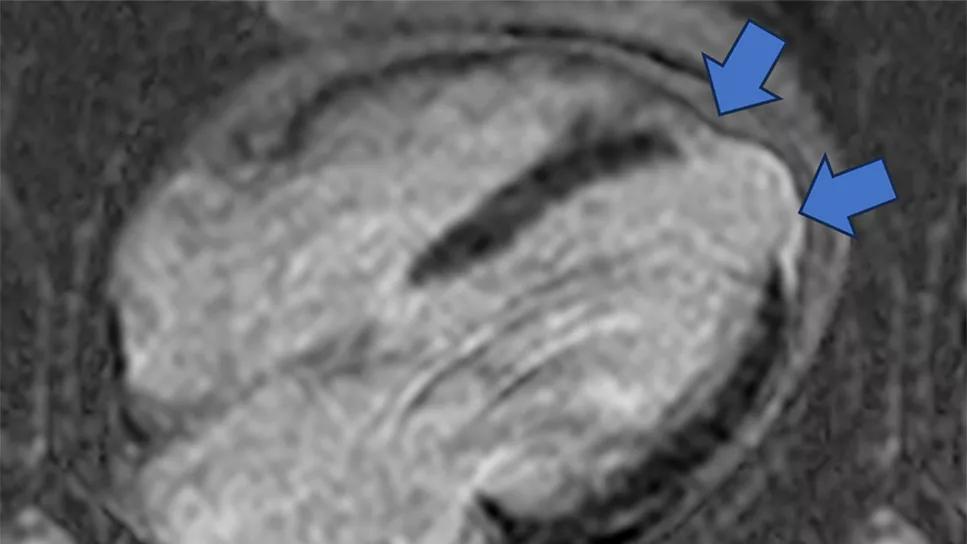

Phenogroup 1 (Figure 1) was defined by intermediate infarct size and limited remodeling; phenogroup 2 (Figure 2) by small infarct size, intermediate remodeling, multi-vessel coronary artery disease and significant secondary MR; and phenogroup 3 (Figure 3) by large infarct size, advanced remodeling and more significant secondary MR.

Figure 1. Representative cine SSFP (steady-state free precession) images (top rows) and late gadolinium enhancement images (bottom row) from a phenogroup 1 patient. Blue arrows indicate areas of late gadolinium enhancement that identify myocardial scarring from prior myocardial infarction.